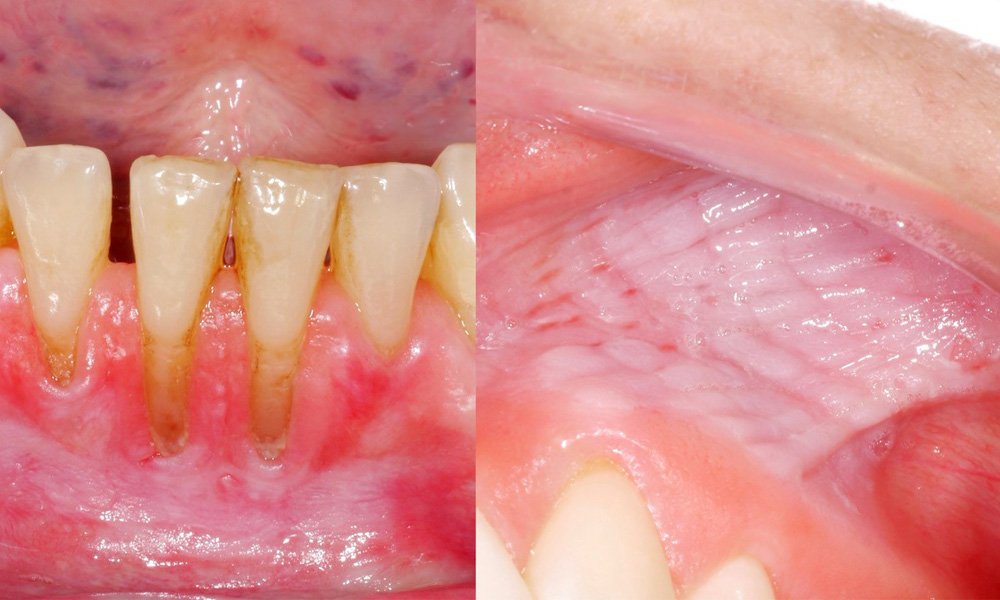

Examinarea clinică a relevat faptul că un consum regulat de snus poate determina următoarele efecte asupra mucoasei orale:

- Aproximativ 80% dintre participanții la studiu, care consumau snus zilnic, prezentau leziuni mucozale induse de snus.

- Aproximativ 20% dintre participanții la studiu, care consumau zilnic snus, prezentau recesiune gingivală indusă de snus.